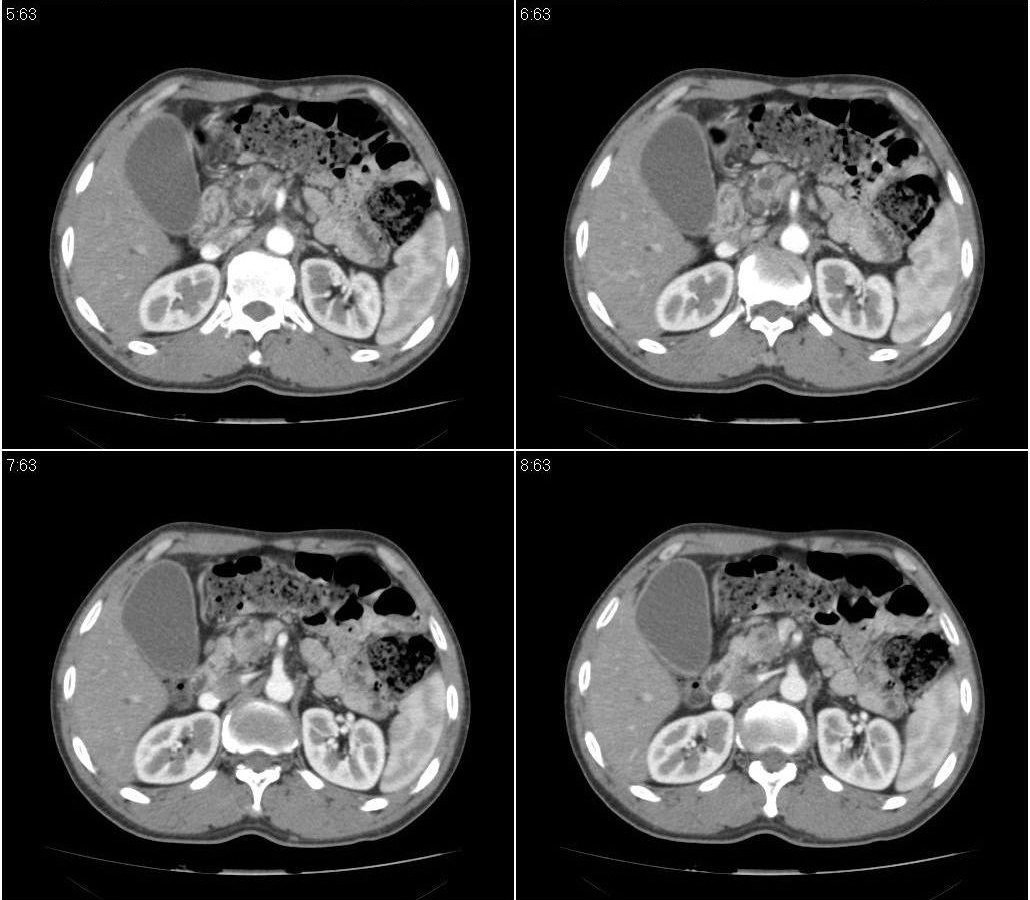

标题: CT21384:男性,50岁。发现无痛性黄疸十余天,B朝提示肝胆管 [打印本页]

标题: CT21384:男性,50岁。发现无痛性黄疸十余天,B朝提示肝胆管

1.考虑:壶腹占位病变(癌?)。

2.胆系低位梗阻:肝内外胆管扩张,胆囊增大,胰管扩张。

胰头癌伴低位胆道梗阻。

胆系低位梗阻(肝内外胆管扩张,胆囊增大,胰管扩张);考虑胰头癌或壶腹癌所致。

胰头强化欠均匀,胆胰管扩张。考虑胰头癌可能性大。

胆系低位梗阻(肝内外胆管扩张,胆囊增大,胰管扩张,钩突似有占位);考虑胰头癌